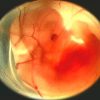

Abortion is Child Sacrifice